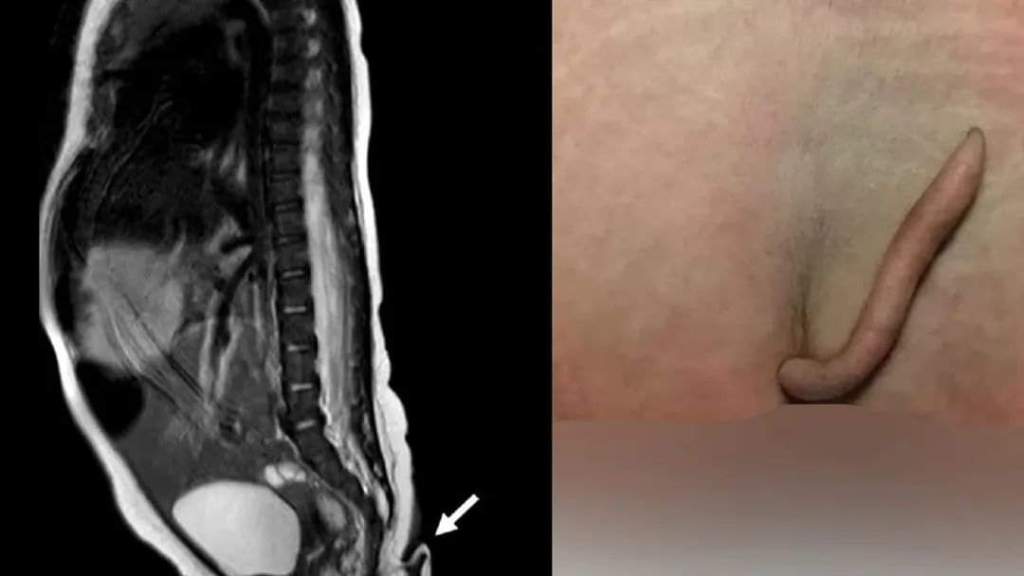

Fue hasta que estuvo fuera del vientre de su madre que los doctores detectaron que la recién nacida presentaba una estructura en forma de cola de 5.7 cm de longitud y de entre 3 y 5 mm de diámetro. La extremidad se encontraba en la hendidura interglútea.

La estructura de la cola era blanda, cubierta de piel y pelo fino, se podía mover pasivamente sin dolor, pero no mostraba ningún movimiento espontáneo. Al detectarlo, los médicos procedieron a pellizcar la extremidad con una aguja, al hacerlo la bebé lloró, por lo que confirmaron una conexión nerviosa.

Asimismo, la resonancia magnética practicada no reveló anormalidades cerebrales, además, fue negativa para disrafismo posterior, y presentó médula espinal y cono medular de características normales. Entre tanto, la exploración auditiva y cardíaca fue normal, es decir: una bebé sana, por lo que fue dada de alta para seguimiento ambulatorio.